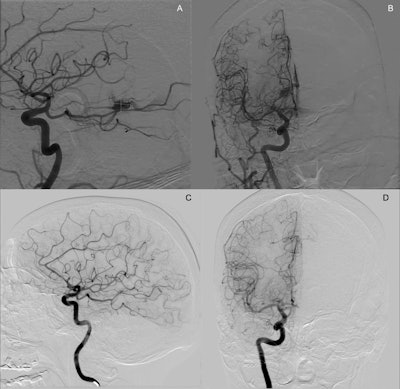

Digital subtraction angiography images in a 65-year-old female patient with a right thalamic arteriovenous malformation (AVM). (A) Lateral digital subtraction angiography image of the right internal carotid artery in the arterial phase shows a compact AVM nidus located in the right posterior thalamus, supplied by distal branches of the posterior cerebral artery via a fetal-type posterior cerebral circulation. (B) Anteroposterior digital subtraction angiography image from the same diagnostic angiogram demonstrates deep venous drainage. The patient underwent Gamma Knife (Elekta) stereotactic radiosurgery four months later, with a single-fraction dose of 20 Gy using cobalt 60 energy, prescribed to the 68% isodose line across 14 shots. (C) Lateral digital subtraction angiography image at 3-year follow-up shows no residual arteriovenous shunting, consistent with complete angiographic obliteration. (D) Corresponding anteroposterior digital subtraction angiography image at the same time point confirms durable obliteration. Iodinated contrast agent (Omnipaque, GE HealthCare) was used for all angiographic acquisitions.RSNA

According to the results, at last follow-up, stereotactic radiosurgery (SRS) achieved complete obliteration of AVMs in 61 of 86 patients (71%) compared with 10 of 18 patients (56%) in the embolization group. The SRS group also had higher rates of modified Rankin Scale scores 0-2 at last follow-up (95% [86 of 91 patients] vs. 71% [15 of 21 patients]), the researchers reported.